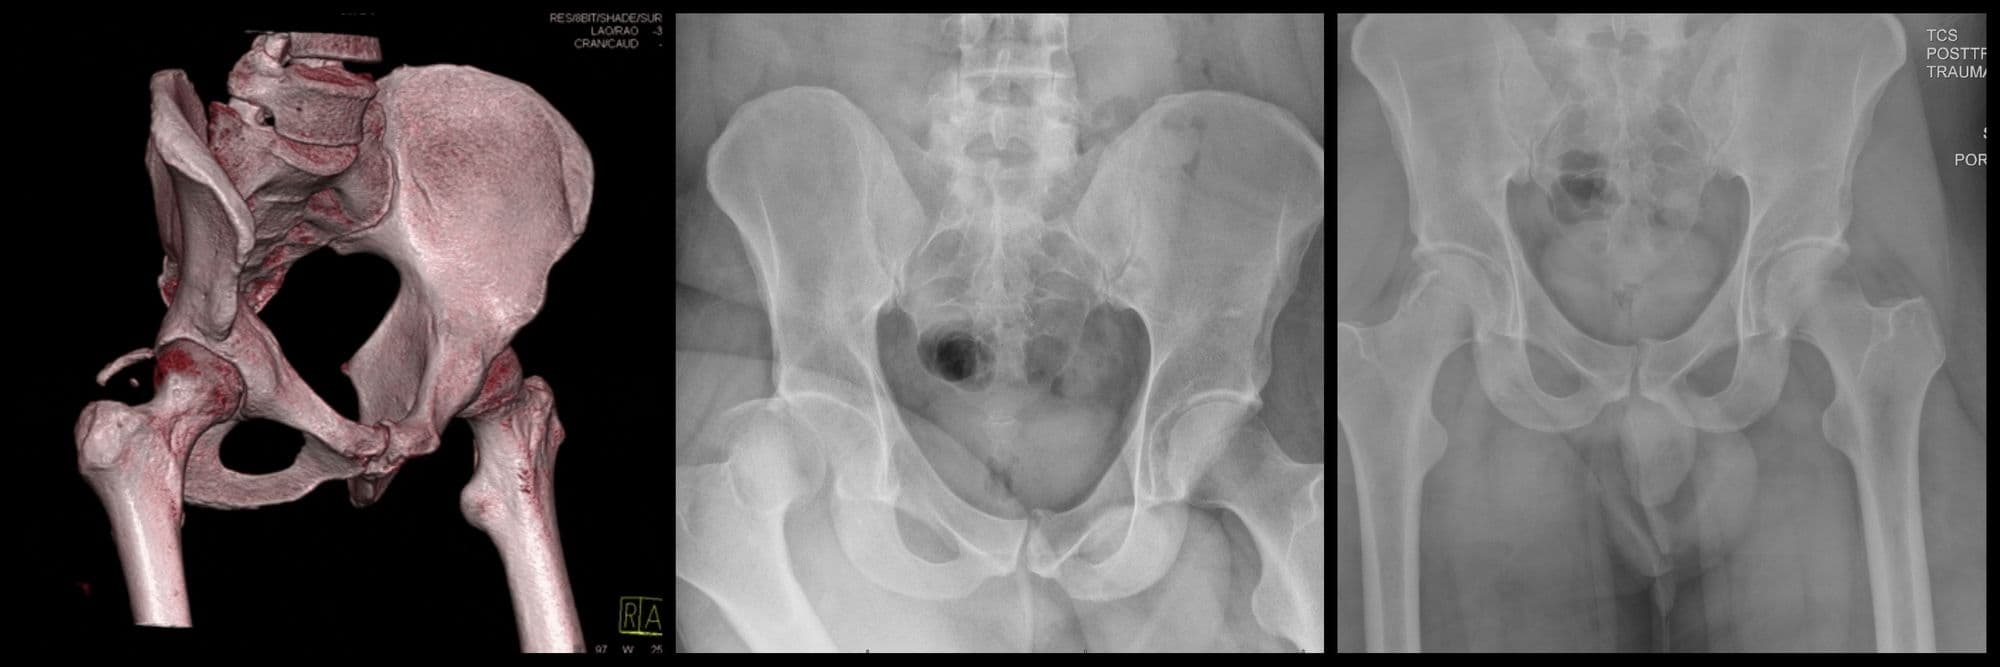

Anterior Column Acetabulum ORIF